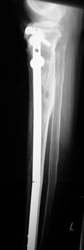

Tibiakopffraktur mit Tibiaschaftfraktur. Geschlossene Nagelung. Nach 3 Wochen volle Belastung. Die rechten zwei Röntgenbilder zeigen den Befund nach einem Jahr.